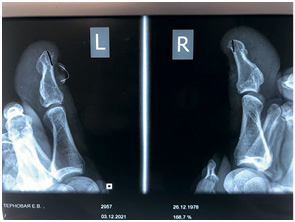

Иллюстрация к книге — Подология понятно. Важен каждый шаг. Справочник по проблемам подологии для клиентов и мастеров эстетики [i_273.jpg]

На этом снимке отчетливо виден экзостоз